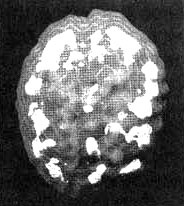

Провести его оказалось нелегко. Мы пытались провести сканирование три раза. Первые два раза она вырывала из вены иглу, утверждая, что мы хотим ее отравить. В третий раз нам удалось провести обследование, поскольку рядом стояла ее сестра, которая разговаривала с ней на всем протяжении процедуры. Результаты показали повышенную активность в глубокой лимбической системе, но не только. Я обнаружил очаги повышенной активности в левой части мозга и участки выраженного повышения активности по всей коре. Иными словами, в каких-то областях отмечалась повышенная активность, а в других — пониженная. Из своего опыта я знал, что циклические нарушения эмоционального состояния часто сочетаются с очагами повышенной активности в глубокой лимбической системе и с участками повышенной активности по поверхности всего мозга.

Мозг Сары — маниакально-депрессивный синдром

Иллюстрация к книге — Измените свой мозг - изменится и жизнь! [i_033.jpg]

Трехмерное изображение активного мозга — вид сверху. Обратите внимание на участки повышенной активности, разбросанные по всей поверхности коры.